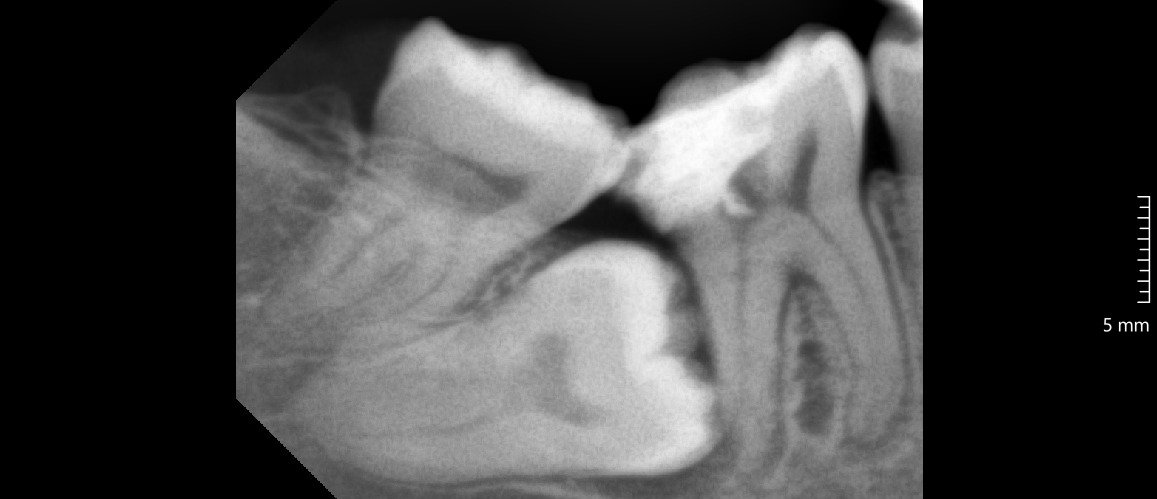

Odontektomi adalah prosedur bedah gigi untuk mengangkat gigi yang sulit dicabut dengan metode biasa. Dokter gigi biasanya melakukan tindakan ini pada gigi dengan impaksi, yaitu gigi yang tumbuh sebagian atau sepenuhnya terpendam di dalam gusi maupun tulang rahang.

Kasus paling sering yang membutuhkan odontektomi terjadi pada gigi bungsu (molar tiga). Gigi bungsu yang tumbuh miring atau kekurangan ruang di rahang sering menimbulkan nyeri, infeksi, serta gangguan pada gigi sebelahnya.

• Gigi bungsu impaksi, tumbuh tidak sempurna dan menekan gigi di sebelahnya.

• Kerusakan gigi sebelahnya akibat dorongan dari gigi bungsu.

Dokter melakukan rontgen panoramic untuk melihat posisi gigi bungsu dan menilai kondisi pasien.